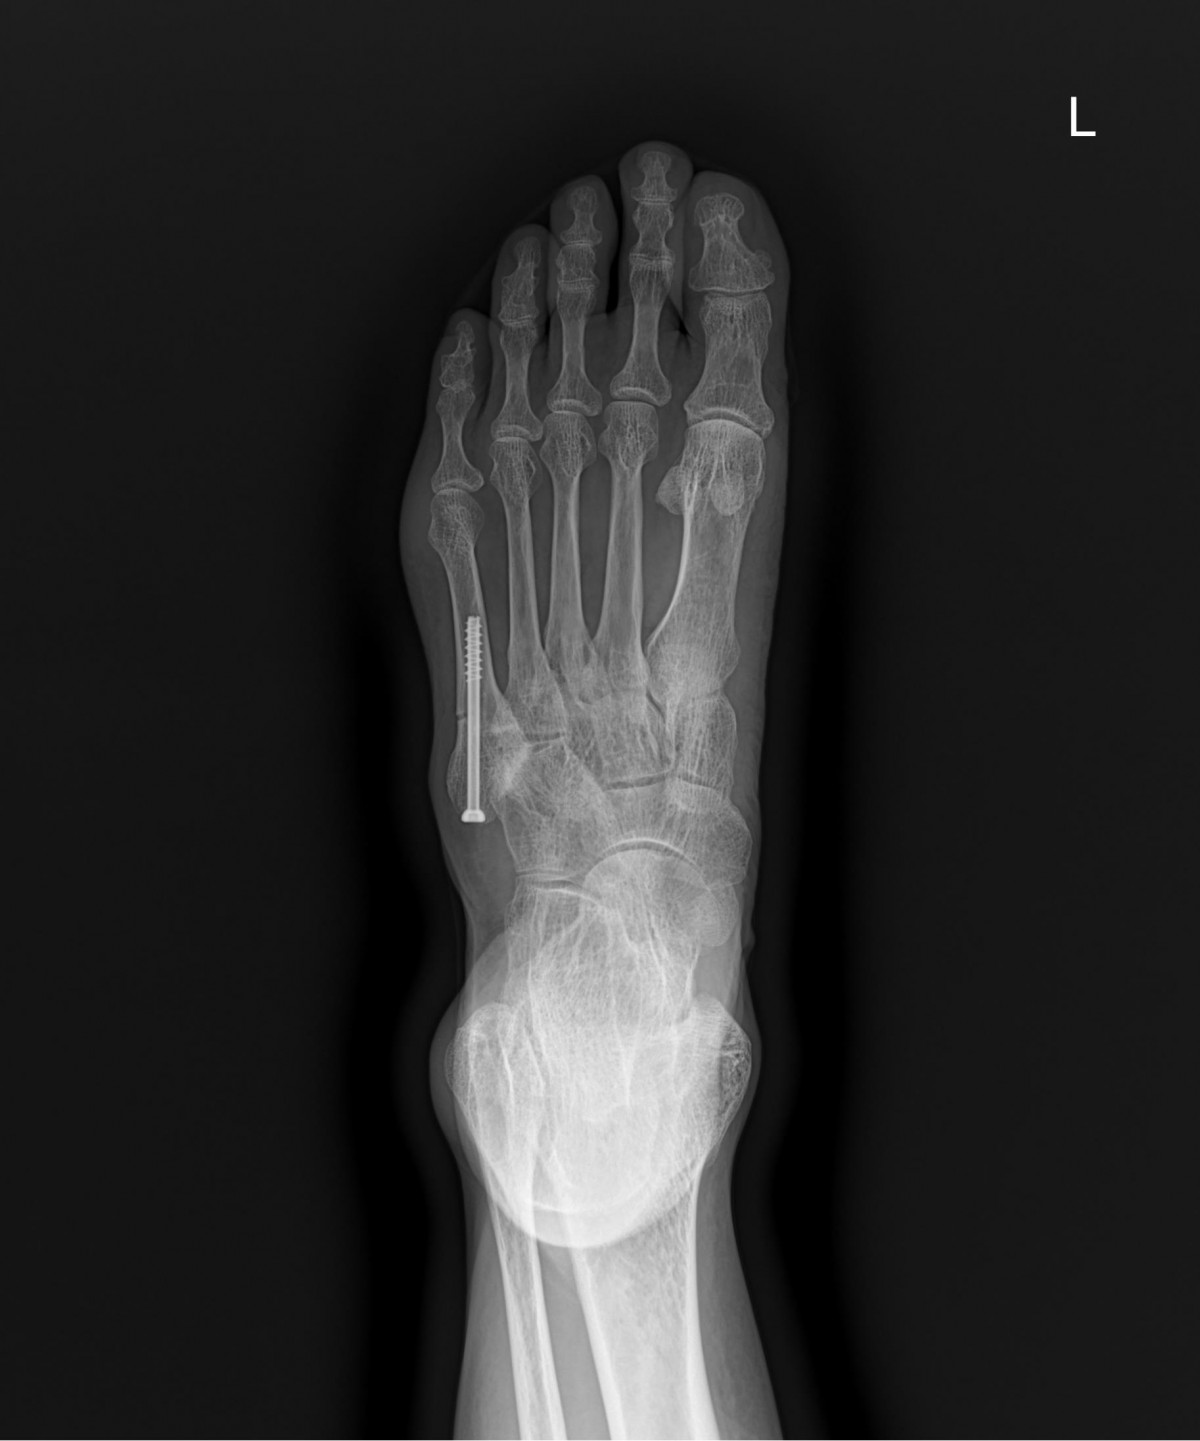

이재상원장님 발등 골절 수술 윤종O 환자

작성자 최고관리자 댓글 0건 조회 1,708회 작성일 24-10-16 16:32

32341c324db2d176f34ec014ac758183_1729063958_6539.jpg

32341c324db2d176f34ec014ac758183_1729063971_733.jpg